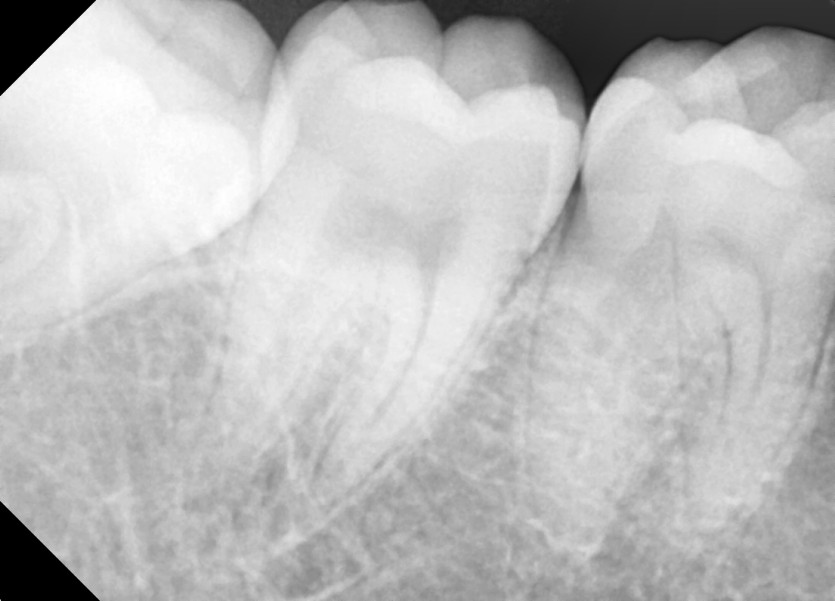

#18,28,38,48 사랑니 발치

구강 외과 전문의가 당일 발치했습니다.